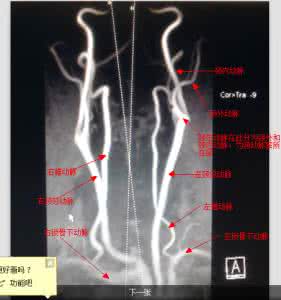

左侧颈内动脉闭塞,左侧颈外动脉分支向脑内代偿供血